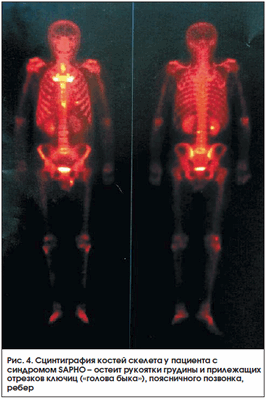

Синдром SAPHO

Синдром SAPHO (Synovitis, Acne, Pustulosis, Hyperostosis, Osteitis) характеризуется кожными проявлениями (ладонно-подошвенный пустулез и/или тяжелое акне) и изменениями в костях (остеит) и суставах (артриты). Данный синдром в связи с множественностью жалоб, разнообразием клинических и рентгенологических проявлений в костной системе может диагностироваться с большим запозданием. Сцинтиграфия костей скелета во многих случаях является методом, дающим достаточную информацию для постановки диагноза. Наибольшее накопление РФП при сцинтиграфии отмечается в зонах усиленного метаболизма кости (остеит) - обычно в костях, образующих грудино-ключичные («голова быка») и грудино-реберные сочленения [33]. Весьма специфичен высокий уровень накопления в трубчатых костях, что чаще встречается у детей (рис. 3, 4).